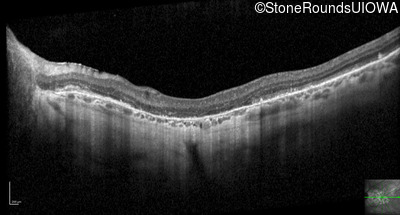

Optical Coherence Tomography - Left - 20/20 -2

Exemplar / OCT Stack

OCT Stack